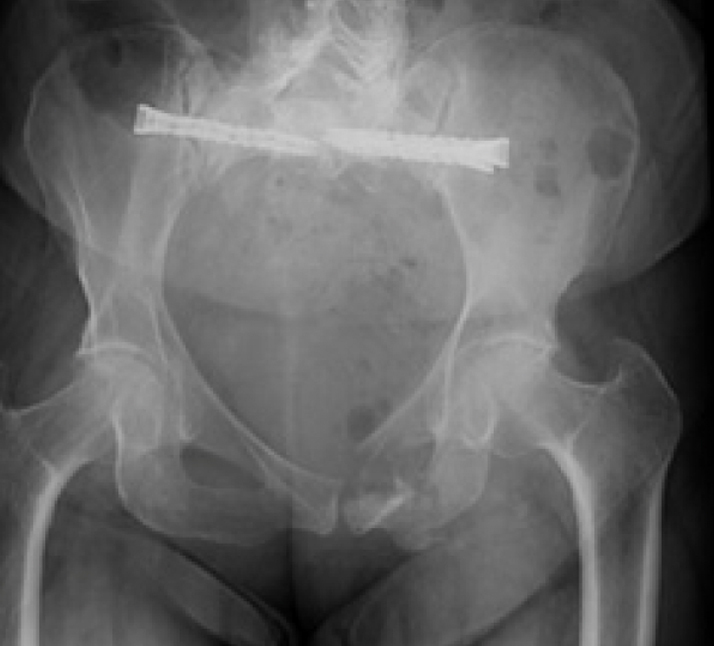

Surgical treatment:

• Bilateral sacral fracture fixation with iFuse TORQ®

Post-op:1,2

• Tolerated procedure well

• Immediate weight bearing as tolerated

• Ambulated 150 feet POD 1 and discharged home

• Pain improvement and healed fracture at 2 months

• No progression of kyphotic deformity